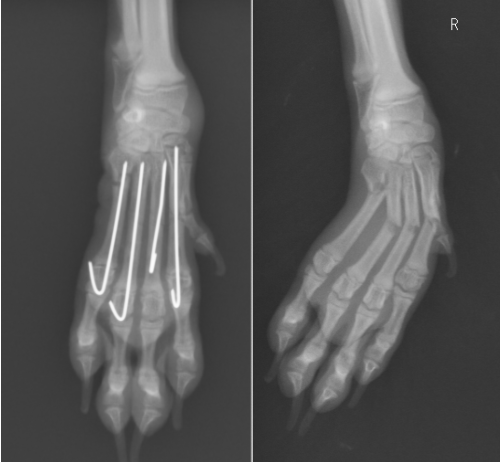

第2〜5指のすべてを骨折しています。この子も0.6mmのピンを使用しています。